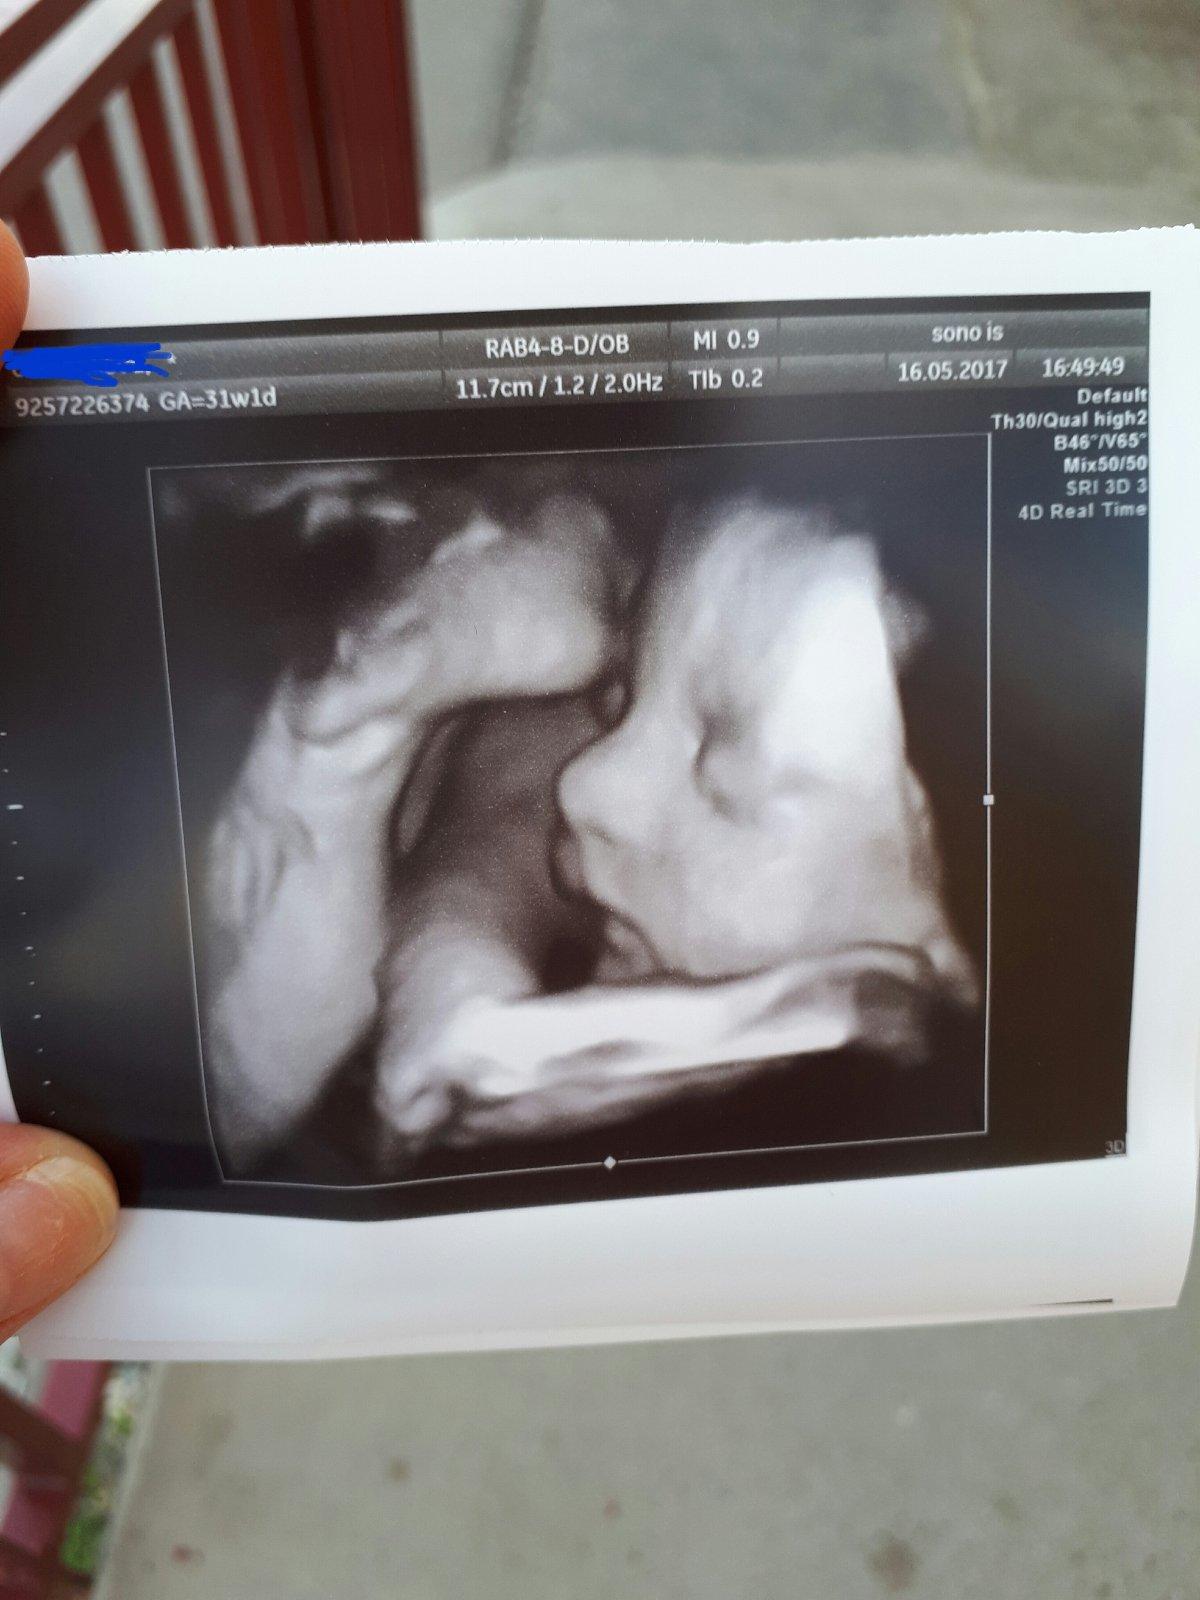

@patkaamirko Moja, ani sa mi nechce veriť, že už si v 30 týždni... Držím palce, nech to spolu s bábätkom potiahnete čo najdlhšie...

@kudusko, a vsetky ostatne kocky, chcela by som sa vam pochvalit mojim malym piskotom 😇 foto sona je sice dva tyzdne stare ale nevadi 🤗 stihli sme aj tehu fotenie, no v tom teple to uz nebola ziadna slava sa valat po zemi 😅 ale tak co clovek neurobi pre krasnu spomienku 😎 zeny, zelam vam krasny slnecny den, my sa uz doma schovavame 😁